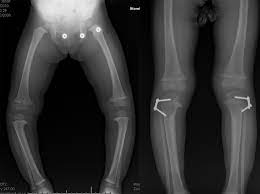

Surgery depending on the type of deformity, surgery may be the best way to permanently correct it. Our surgeons are skilled in applying internal and external rods, plates and frames to help lengthen or straighten the affected limb.